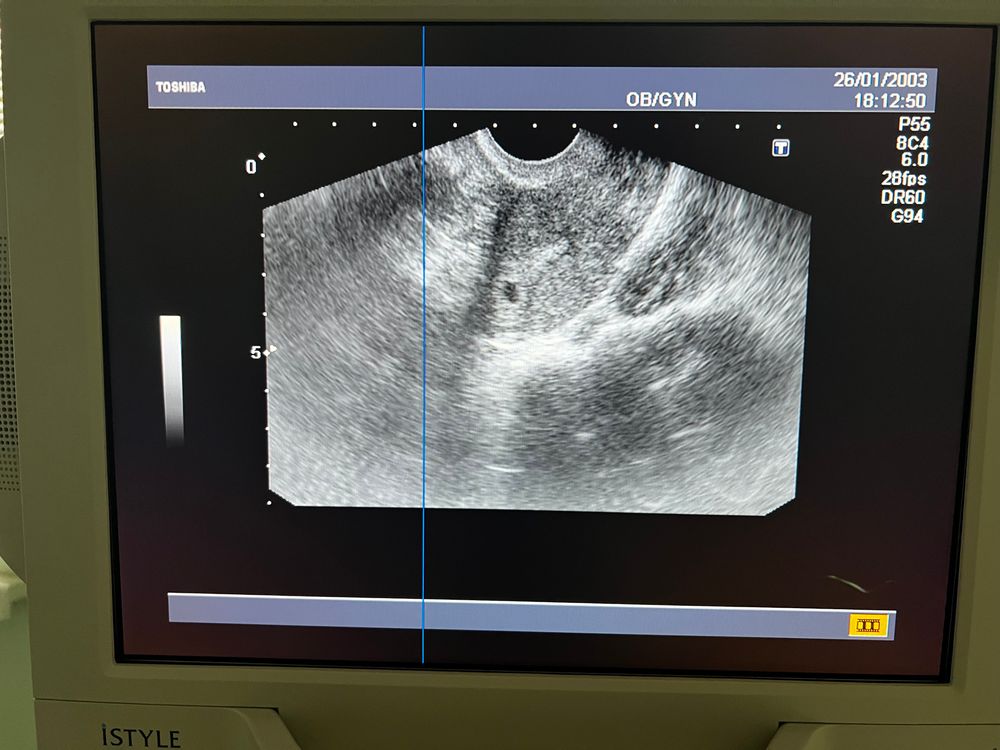

Такого размера ещё сомнительно,может быть что угодно,были тут пя находили якобы тоже очень маленькое,а по факту совсем не пя и внематочная в итоге была,точно пя это когда в нем есть желточный мешочек или размер побольше,на фото вашем точка 2-3 мм,вот мое УЗИ в 5 акушерских недель Изображение